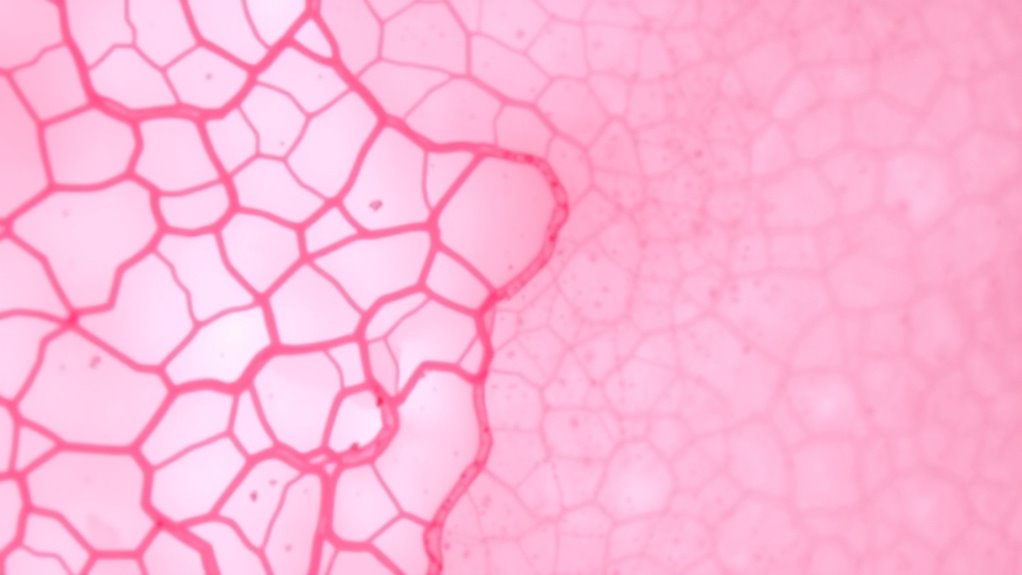

Pathologische Merkmale und Klassifikation von DCIS und LCIS

Das Verständnis der pathologischen Merkmale und der Klassifikation von DCIS und LCIS ist entscheidend für eine genaue Diagnose und Behandlung. DCIS, auf die Milchgänge beschränkt, erscheint als anormale Zellproliferation, die die Basalmembran nicht durchbricht. Es wird in Untertypen wie Komedo und Nicht-Komedo eingeteilt, die sich in Wachstumsmustern und Progressionsrisiko unterscheiden. LCIS entsteht in den Lobuli und gilt eher als Risikomarker denn als echtes Krebsleiden. Es zeigt einfache, kleine Zellen, die die Lobuli füllen, oft mit klassischen lobulären Merkmalen. Die Klassifikation basiert auf dem histologischen Erscheinungsbild, der Zellarchitektur und molekularen Markern. Das Erkennen dieser Merkmale hilft, nicht-invasiven von invasiven Läsionen zu unterscheiden und die Behandlungsentscheidungen zu lenken. Der Einsatz von molekularen Markern verbessert die Genauigkeit der Klassifikation und unterstützt personalisierte Behandlungsansätze.